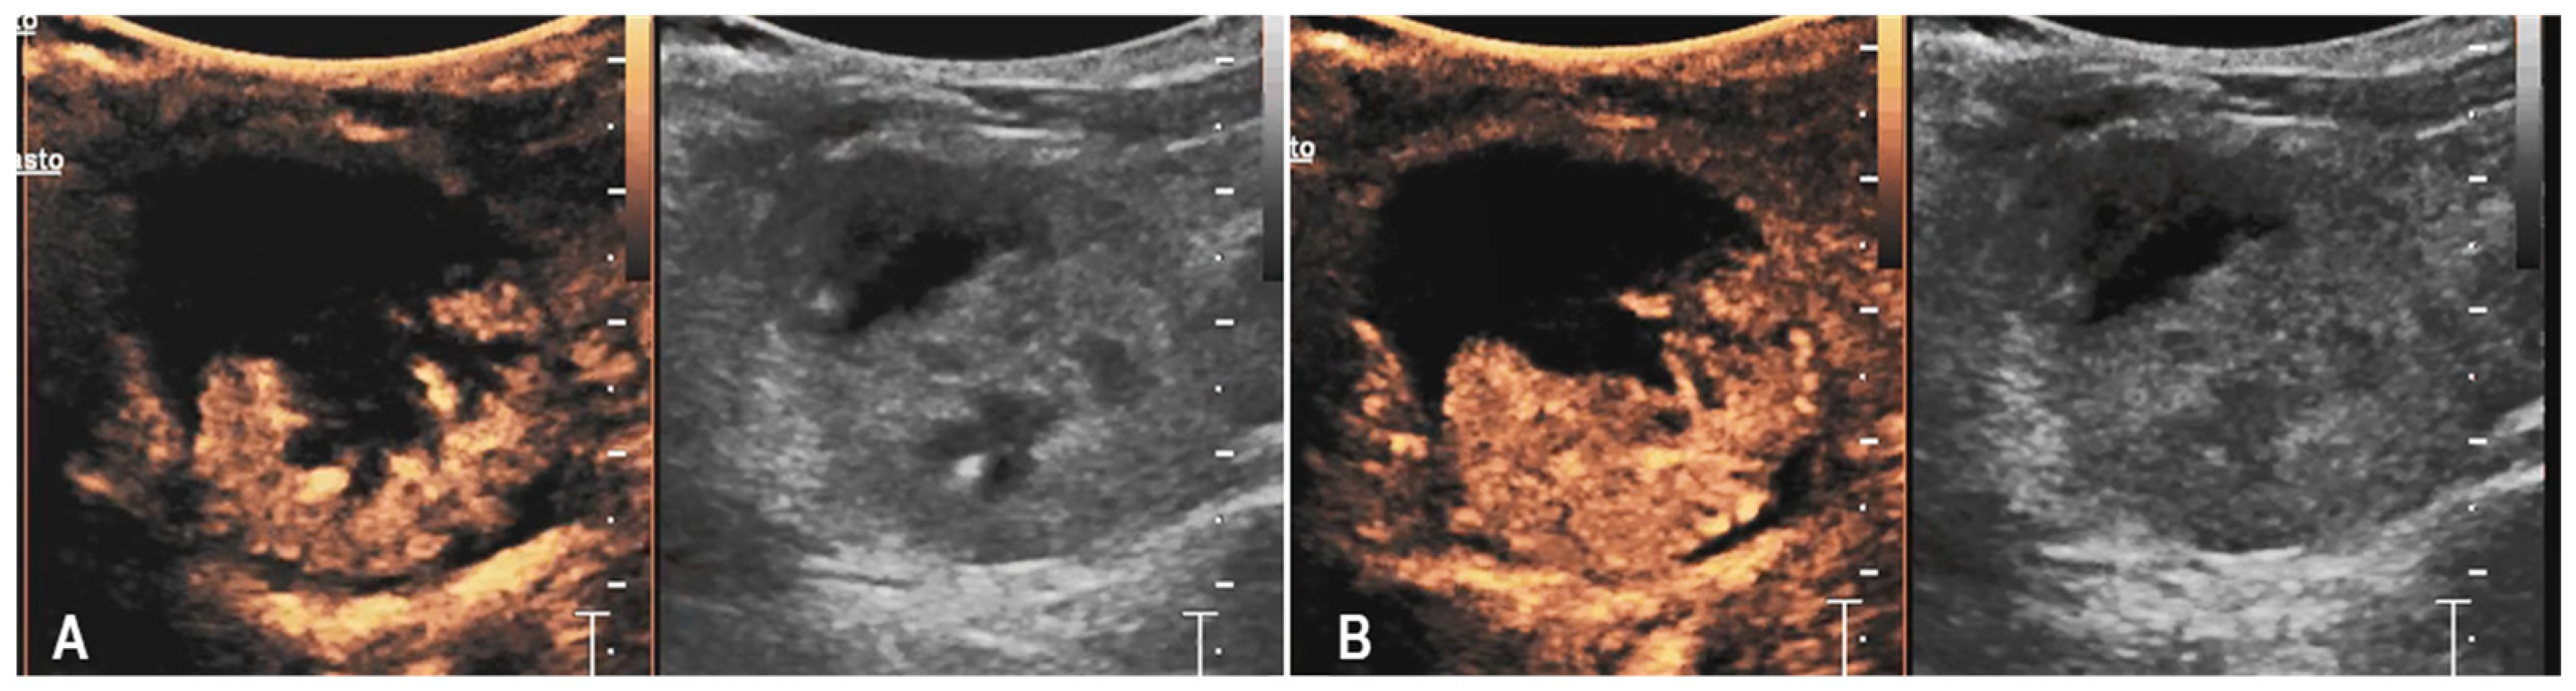

3.2. Case 2

3.3. Case 3